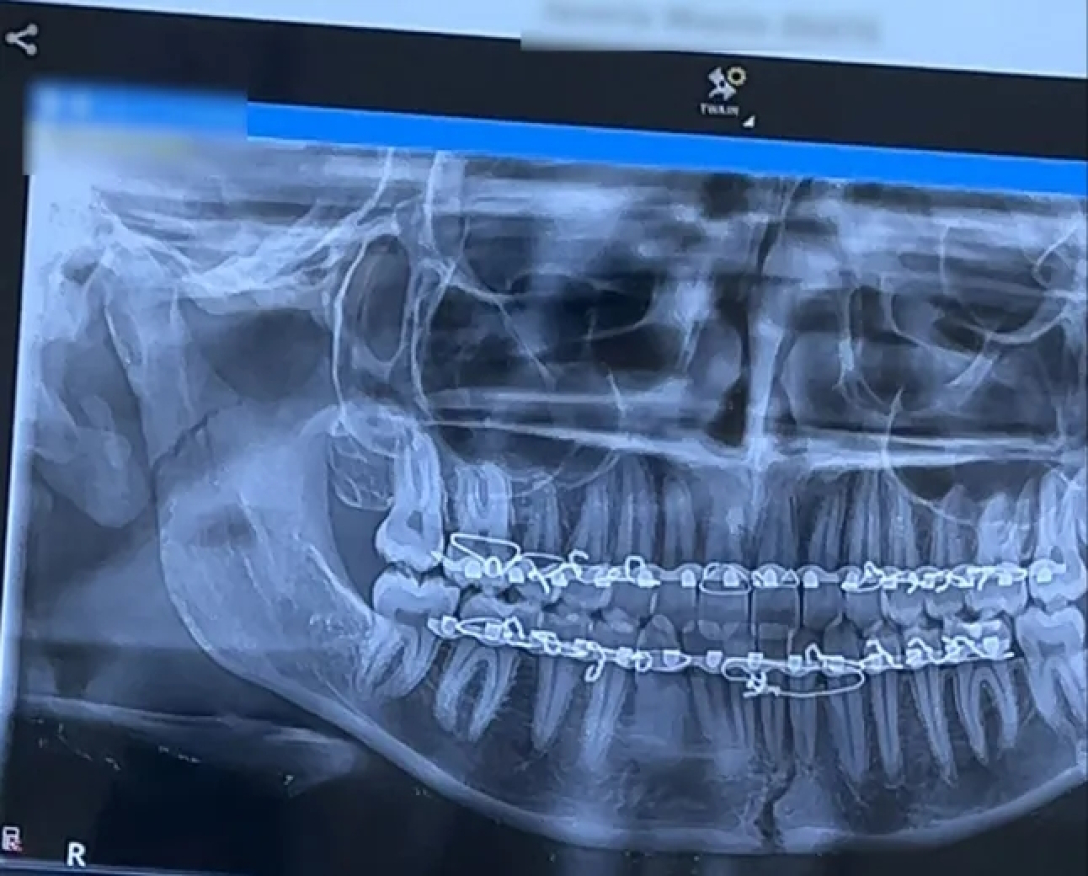

У лікарні рентген і комп’ютерна томографія показали, що в дівчини два переломи щелепи.

Після годинної процедури щелепу повернули на місце, а на верхні та нижні ясна встановили пластини, зафіксувавши їх дротом на шість тижнів.